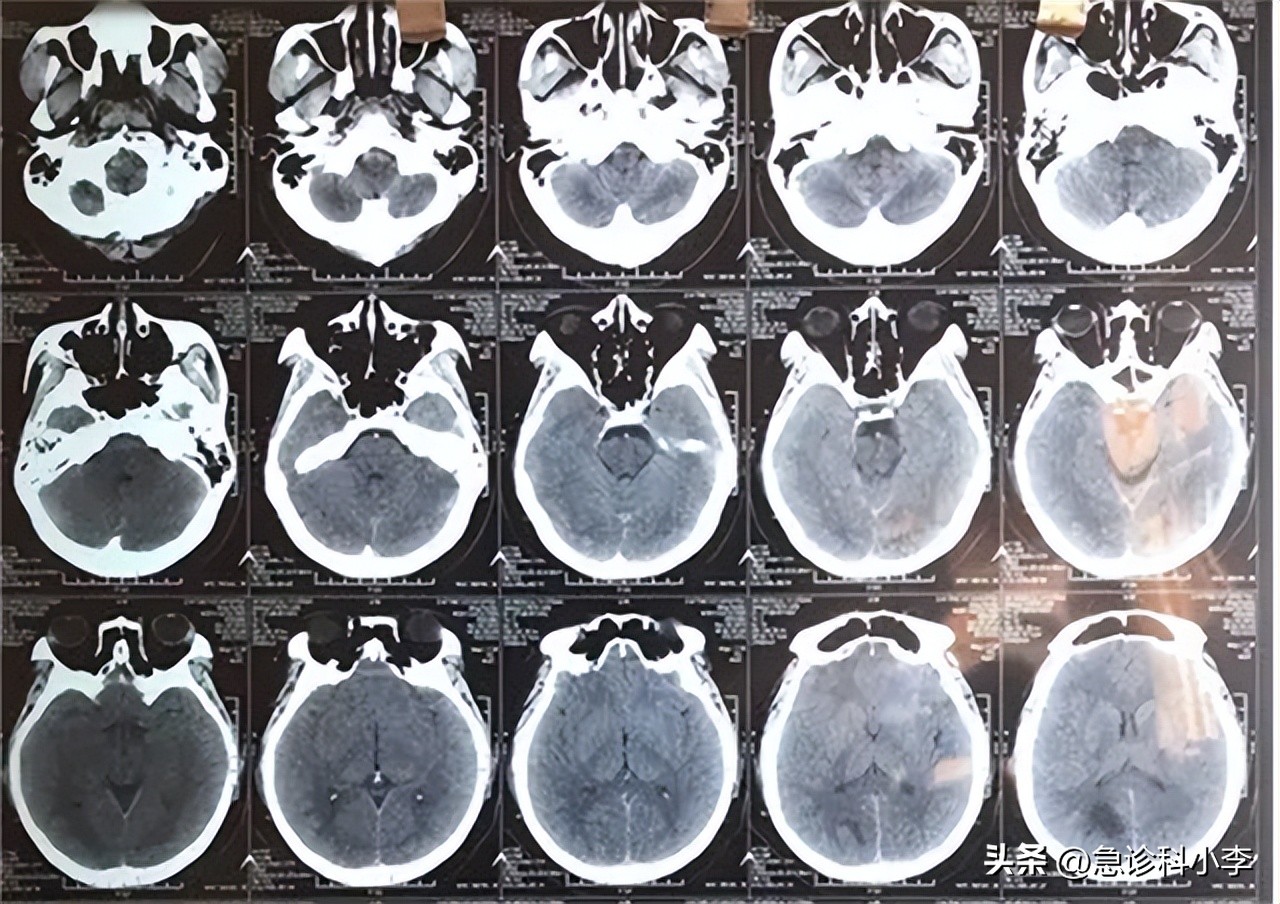

起初他以为是自己学习过于劳累以及近视加深所致,但是休息了几天也不见好转,在咳嗽时更是头疼难忍,小谷的父母这才意识到这可能并非简单的头疼和近视,当即带小谷去医院进行了检查, 随后在医生的建议下进行了头颅CT、磁共振平扫等检查后,确诊为恶性脑胶质瘤。

如果经常有不明缘由的头疼以及癫痫情况发生时,就要考虑是否为脑胶质瘤的早期症状,此时应及时去医院进行科学检查,就诊做 磁共振和CT检查 就能确定是否存在脑胶质瘤。